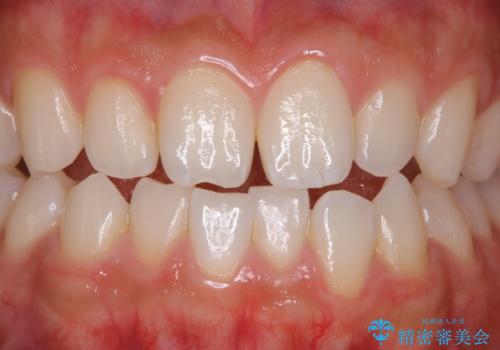

- 前歯をきれいにしたいとのことで来院されました。歯科医院でのクリーニングは半年ぶりでしたが、今回は前歯をメインにクリーニング希望だったためPMTCの30分コースを行いました。

前歯をメインに行う30分5000円+taxと全体的に行う60分10000+taxコースです。お口の状態や、ご希望により、担当衛生士と相談をしてからの施術となります。

今回は、前歯メイン希望とのことでしたが、歯石やプラークが薄い付着だったため、30分コースの中で全体的クリーニングが行えました。